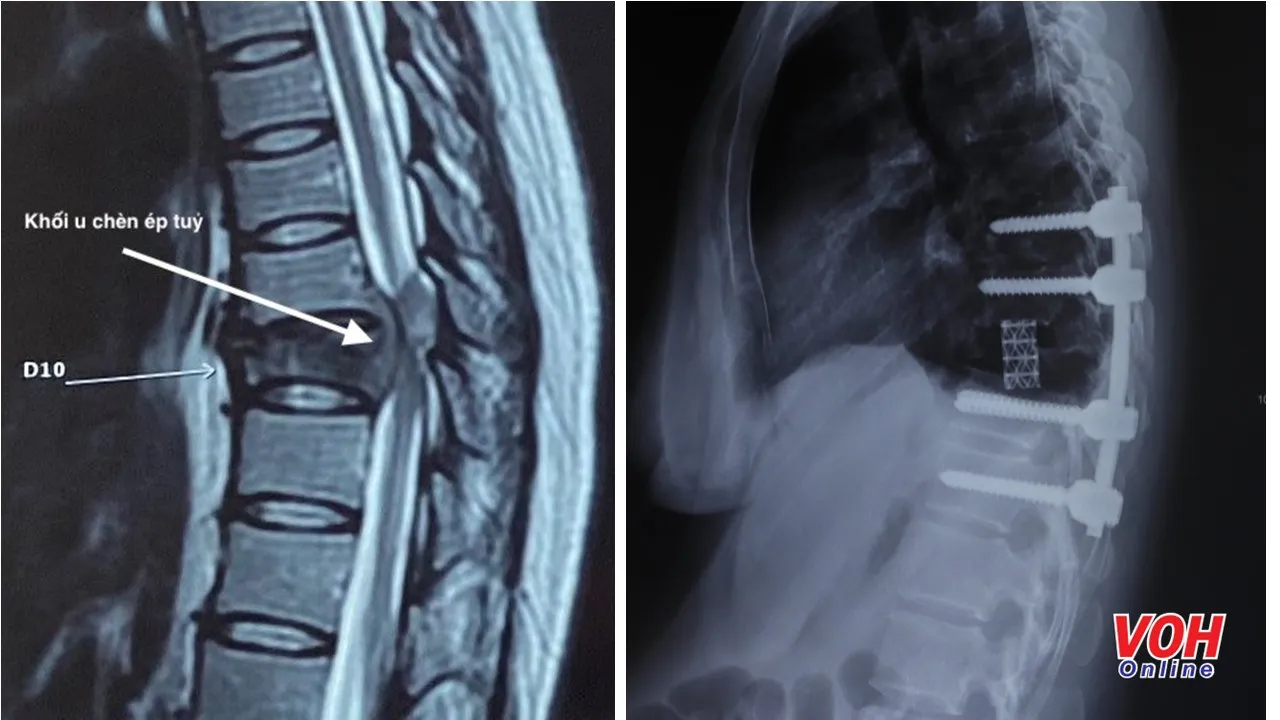

Sau khi thăm khám, đánh giá mức độ vận động của chi dưới và xem xét kết quả MRI, ThS.BS Trần Đức Duy Trí – khoa Ngoại Chấn thương chỉnh hình Bệnh viện Hoàn Mỹ ITO Đồng Nai cho biết: “Qua hình ảnh MRI cho thấy, bệnh nhân K. bị khối u chèn ép vào tủy gây tổn thương nặng thần kinh thân sống và làm cho thân sống bị mất vững nên việc quan trọng đầu tiên là phải phẫu thuật giải phóng được chèn ép tủy của bệnh nhân.

Điểm phức tạp ở ca phẫu thuật này là khối u thân sống chèn ép thần kinh, nên muốn giải phóng thần kinh phải bóc u và cắt toàn bộ phần thân sống bị hư nếu không nguy cơ tái phát cao”.

Theo đó, bác sĩ Trí cùng ê kíp phẫu thuật đã tiến hành cố định cột sống bằng bắt vít cuống cung từ đốt sống D8 đến D12 lối sau. Sau đó, khối u được lấy hết đồng thời toàn bộ thân đốt sống D10 được cắt bỏ hoàn toàn để giải phóng thần kinh bị chèn ép.

Cuối cùng lồng kim loại được đặt vào giữa thân sống từ D9-D11 để thay cho thân sống D10 bị hư, như vậy toàn bộ cột sống về lâu dài sẽ vững chắc hơn.